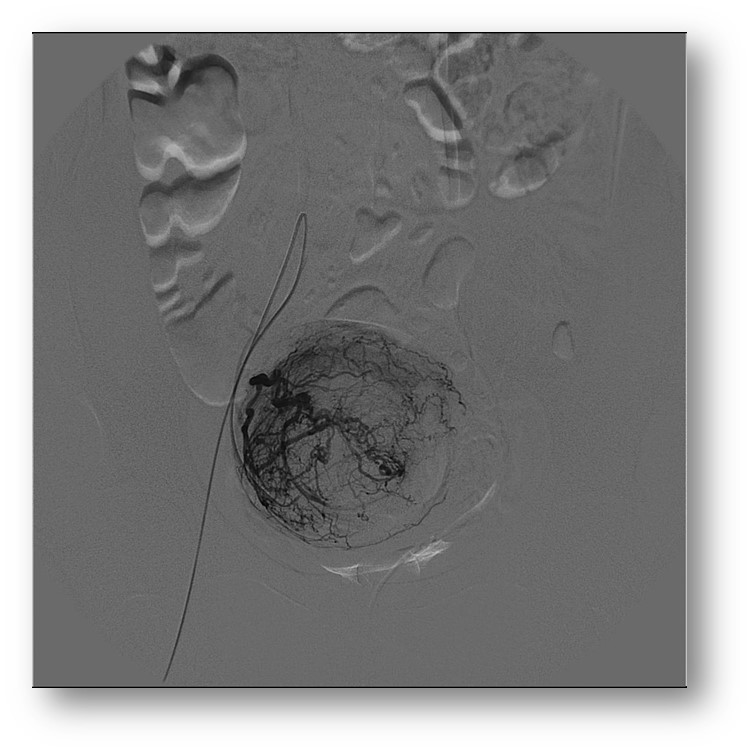

A embolização é um procedimento minimamente invasivo que consiste em uma

punção na região da virilha seguido de inserção de um fino catéter que vai até

a região dos miomas. Através deste catéter são injetadas partículas que são

pequenas bolinhas que ocluem a irrigação de sangue para os miomas. Assim os

miomas regridem e deixam de causar sintomas.